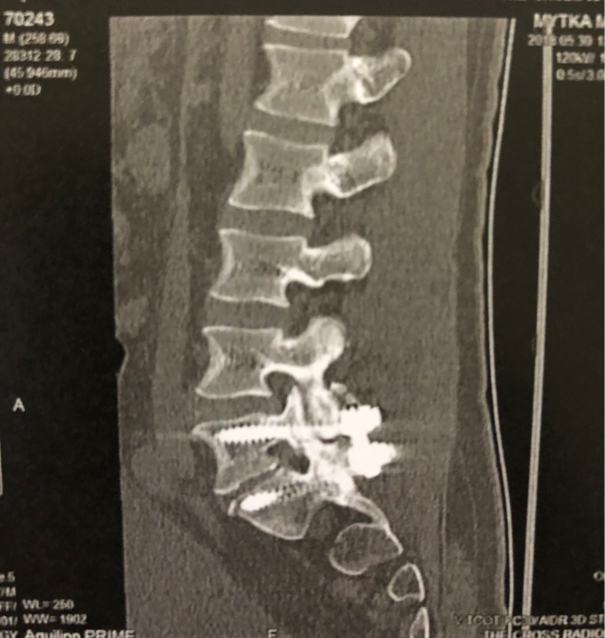

My back had been sore from a workout session the day before (old back injury playing up) so I stayed in bed. I'd been up late reading about complex systems (great bedtime reading 🤦♂️) because my back pain was keeping me from sleeping.